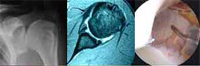

Imagen de rayos X, resonancia magnética y artroscopia

- Tendinitis calcificante

El manguito rotador puede presentar una calcificación de pequeño tamaño asociada a una tendinitis del hombro. El síntoma principal es el dolor, a menudo nocturno y muy intenso, que empeora al levantar el brazo. También puede existir debilidad.El tratamiento inicial es conservador: medicación y fisioterapia, siendo necesario en ocasiones realizar infiltraciones. Si no existe mejoría el tratamiento es quirúrgico. Se realiza una artroscopia del hombro y se elimina la calcificación.

Después de la cirugía se coloca el brazo en un cabestrillo y se realiza un programa de rehabilitación. La recuperación es satisfactoria en unos meses.